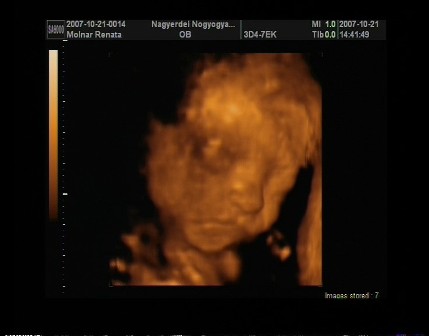

Egézséges kislányom lessz!Néhány fotó!!!! Kép Kép Kép Kép

m. reni